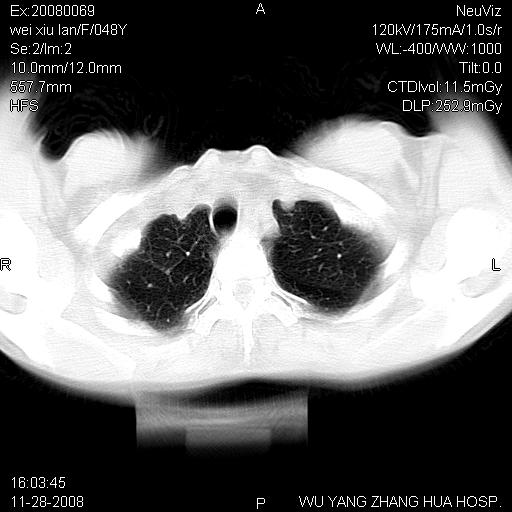

标题: CT16847:女,48岁,咳嗽,发热两日,平常偶有上腹部不适。 [打印本页]

标题: CT16847:女,48岁,咳嗽,发热两日,平常偶有上腹部不适。

能否考虑食管裂孔疝?请老师们多多指教。

这个是左侧膈膨升伴不完全性胃翻转,手术将松弛的左横膈膜折叠缝合即解决问题。

支持左侧膈疝,心脏受压右移.

胃、脾脏及部分肠管明显升高,并压迫心脏移位,

首先考虑:左侧膈疝。

左侧胸腔内见胃肠及脾脏影

支持膈疝